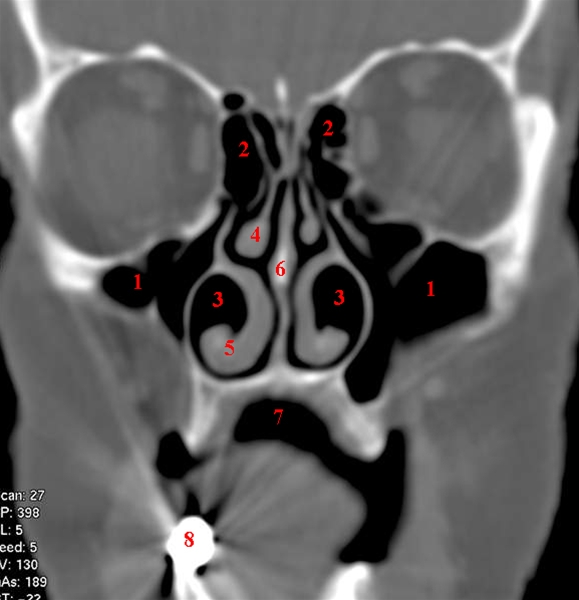

CT-snit i coronalplan gennem forreste del af næse og bihuler.

1. Sinus maxillaris (kæbehulerne)

2. Sinus etmoidales (sibensceller)

3. Cavum nasi (næsehulen)

4. Concha media (miderste næsemusling)

5. Concha inferior (nederste næsemusling)

6. Septum nasi (næseskillevæg)

7. Cavum oris (mundhulen)

8. Tandfyldning, som giver stribeartefakter i billedet